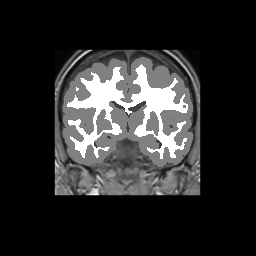

Accuracy is reported as Dice overlaps between a tool's segmentation and the Internet Brain Segmentation Repository (IBSR) manual segmentation for each of the 18 IBSR subjects. The inter-tool comparison (on the left below) shows the median Dice coefficient for each tissue class. The overlaps for FSL (from which the median values are drawn) are shown in the plot on the right.

Subject Accuracy (IBSR)

Overlap coefficients for each tissue class are shown here for each IBSR subject. Select a subject below to see the FSL results compared to other tools.